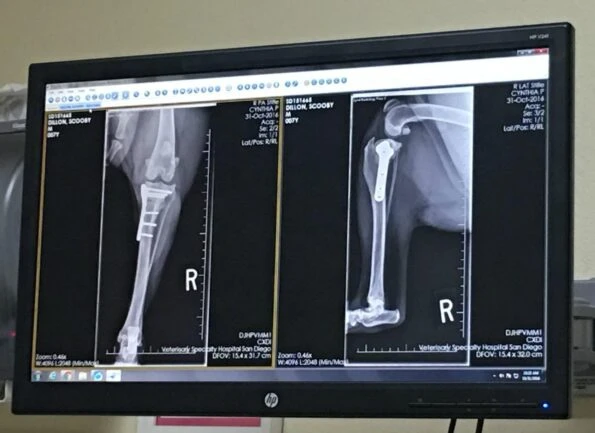

We headed back to the surgeon for a routine check-up. This is where they take further radiographs to see how the bone has healed. Because he needs to be sedated for radiographs, he was not allowed to eat anything after midnight the night prior.

Everything looked good. By this point in TPLO recovery, most dogs have 100% bone healing. However, Scooby only had 80%. The surgeon wasn’t at all worried about it because we were going to rehab. He looked great and was walking fine.